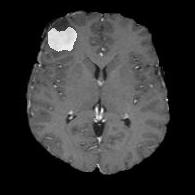

We argue that the sub-optimal paradigm of processing different abstractions within a single CNN pipeline can be remedied through the effective processing of information in a structured manner. Consequently, we devise strategies for disentangling the edge and texture information within a single training pipeline. Figure 2 illustrates how our proposed module, dubbed EG-CNN, can be paired with any existing CNN encoder-decoder to improve segmentation quality near intensity edges. We have applied our EG-CNN to the tasks of brain and liver tumor segmentation in medical images (Figure 3).

(1) Brain MR (2) Liver MR (3) Liver CT (4) Lung CT